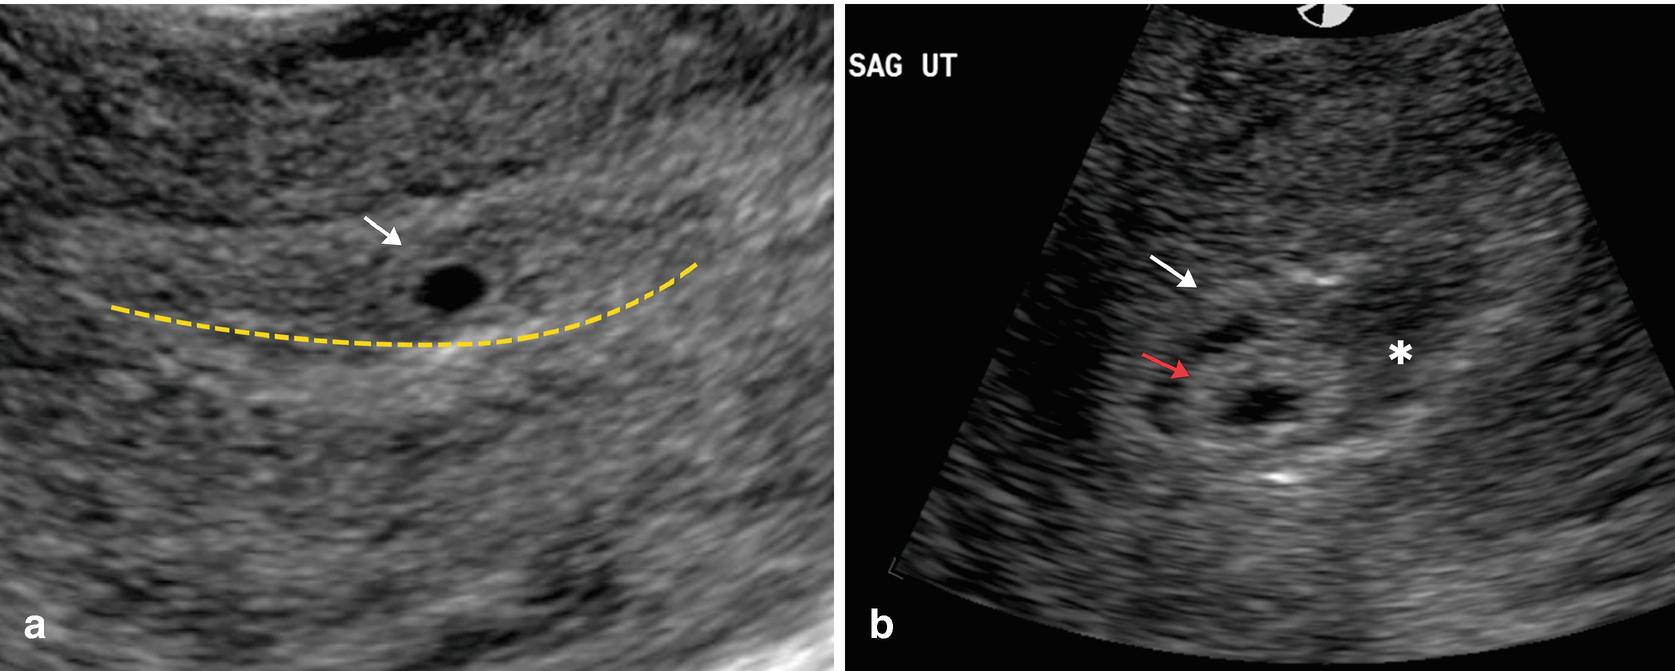

the scan is done over your abdomen and pelvis . The transvaginal ( internal ) ultrasound scan does not require a full bladder as the scan probe is placed inside the vagina and is closer to the pelvic organs being examined . This type of scan is used to help provide clearer pictures of the womb, ovaries and surrounding structures .

Peek A Baby offers Early Pregnancy Reassurance Scans from 6 weeks of pregnancy . In viable pregnancies, trans-vaginal ( internal ) scans should be able to detect a gestation sac from 5 weeks of pregnancy . A yolk sac can be seen at 5 1/2 weeks gestation . Trans-abdominal ( external ) scan may be less accurate at this early 5 week stage .